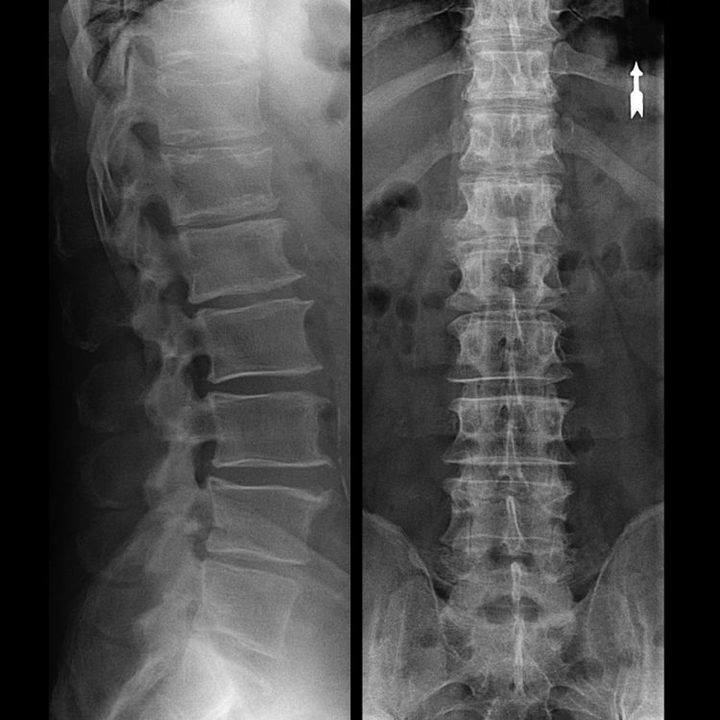

In typical cases, osteochondrosis of the cervical and cervicothoracic spine occurs as described above.Therefore, the main stage of diagnosis was, and still is, identifying the patient's presenting complaint and determining the presence or absence of accompanying muscle spasms by simply palpating the muscles along the spine.Can osteochondrosis be diagnosed through X-ray examination?

An "X-ray" of the cervical spine, even with flexion and extension functional tests, will not show the cartilage because the cartilage tissue transmits the X-rays.Nonetheless, depending on the position of the vertebrae, one can draw general conclusions about the height of the disc, the overall straightening of the physiological curvature of the neck (lordosis), and the presence of growth on the upper edges of the vertebrae and the chronic irritation of its surface by a fragile and dehydrated disc.Functional testing can confirm the diagnosis of cervical spine instability.

Because the disc itself can only be seen with CT or MRI, magnetic resonance and X-ray computed tomography are used to elucidate the internal structure of the cartilage as well as structures such as protrusions and hernias.Therefore, the diagnosis can be made accurately with the help of these methods, and the tomographic results can be used as an indication or even a local guide for neurosurgical hernia surgical treatment.

- You can regularly have at least one lumbar X-ray (two projections) or MRI to see if the hernia (if any) is progressing;